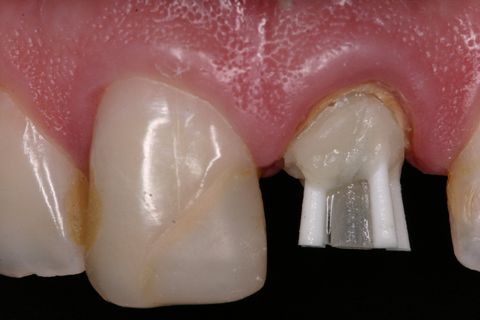

Pino de fibra de vidro #3 (Exacto) pinos acessórios (Reforpin) Angelus, Brasil

Inicialmente, foi removido o tecido cariado do remanescente dental e realizado a seleção do pino de fibra de vidro (Exacto # 3, Angelus, Brasil) e também foram selecionados pinos acessórios (Reforpin, Angelus, Brasil) (Figuras 4).

Isolou-se o conduto radicular com óleo mineral e inseriu-se a resina composta (Fill Magic NT Premium, Coltene-Vigodent, Brasil) sobre o remanescente dentário com auxílio de uma espátula suprafill #1/2 (Figuras 5 e 6). Após o preenchimento do conduto com resina, foi inserido o pino Exacto cônico e os pinos acessórios previamente silanizados (Silano, Angelus, Brasil) e com a aplicação do adesivo (Fusion Duralink, Angelus, Brasil) (Figuras 7, 8 e 9). Em seguida, promoveu-se a fotoativação inicial do conjunto pino-resina por 20 segundos.